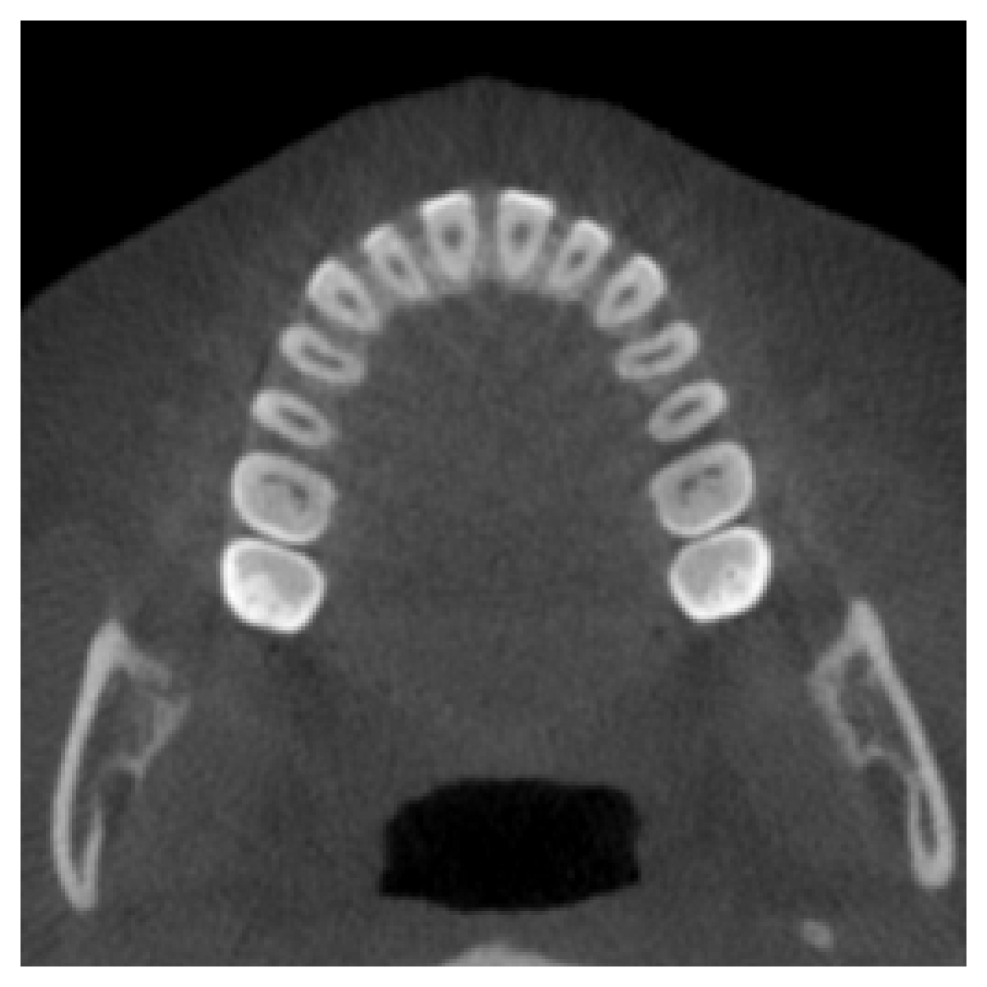

Full Dental Synthesis.

As a final experiment, we evaluate the model’s performance on generating a complete dentition in scans with no teeth present. This assesses the model’s ability to synthesize anatomically plausible full dental structures from the conditioning vector. Fig. 3 presents qualitative results comparing the generated samples to real scans with complete dentition. The visual comparison demonstrates a strong alignment between the real and synthetic inpainted regions. Quantitative evaluation supports this observation, with an average SSIM of 0.9123 and an average PSNR of 18.35 computed over the inpainted areas, despite the model not having seen the test samples during training.

Refer to caption

(a) Real Scan 1

(b) Synthetic Scan 1

(c) Real Scan 2

(d) Synthetic Scan 2

Figure 3: Qualitative comparison between generated CBCT scans and their corresponding real scans with complete dentition.